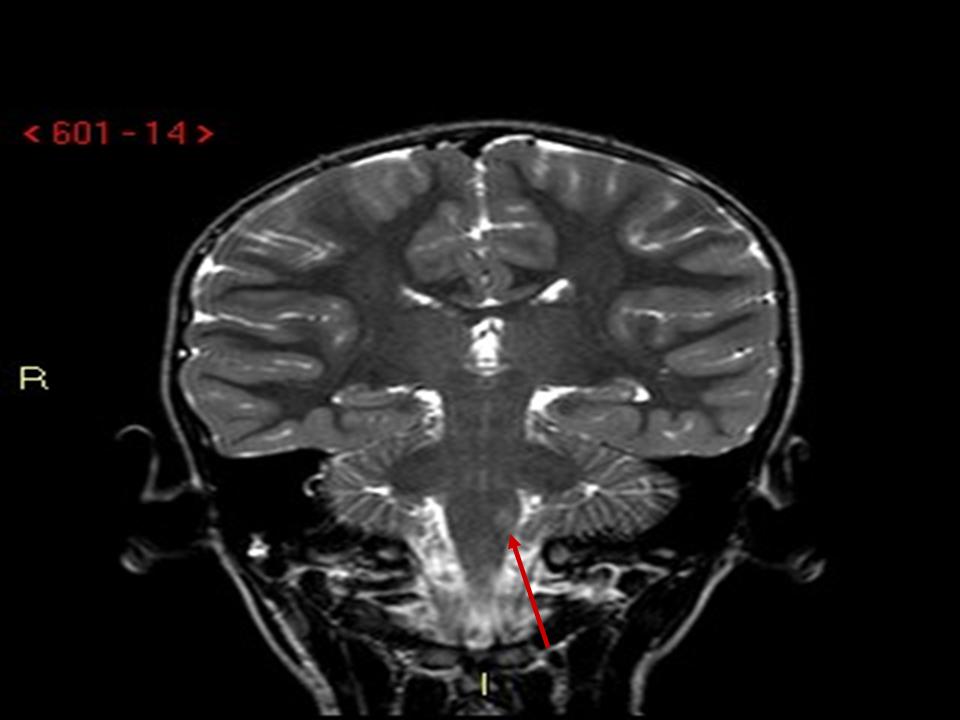

Figura

2. RMN. Coronale TSE T2: piccola lesione iperintensa a carico della porzione posteriore del bulbo compatibile con piccola lesione ischemica recente.